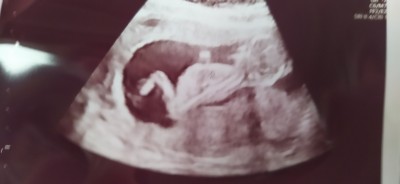

13 haftalık ultrason görüntüsü sizce kız mı erkek mi tahmini olan yazabilir misiniz

Başka ultrason resmi varmi canim

Kıza benziyor dedi doktor bildiniz☺️

Göstermedi dedi bacak arasıni kapatmış

Çikolata yedim meyve suyu içtim ama malesef hemen arkasını döndü